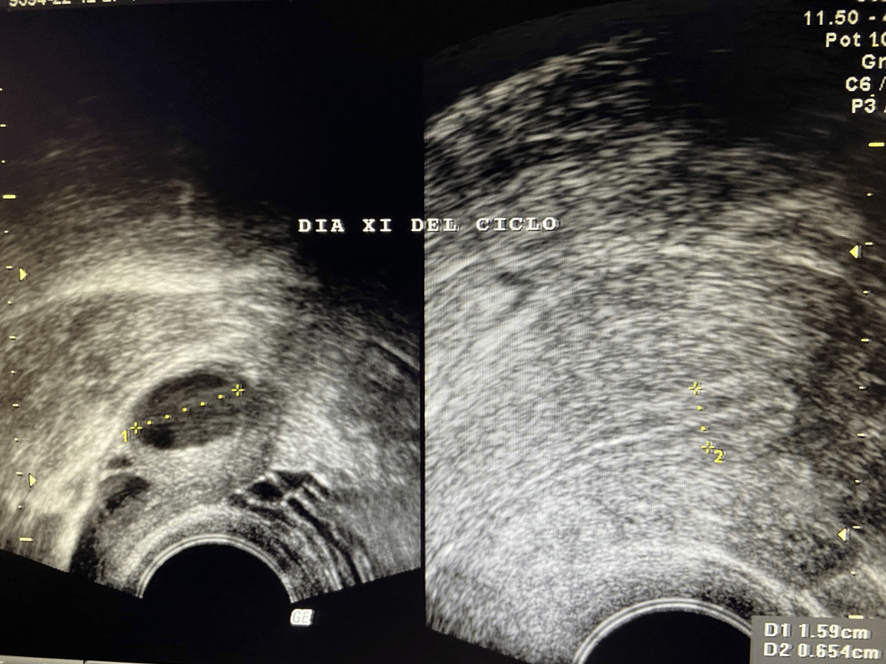

La primera imagen ecográfica de un embarazo la podemos obtener a las 4 semanas de gestación, cuando la embarazada solo lleva 2-3 días de atraso menstrual. Corresponde a una pequeña burbuja negra rodeada de un fino anillo blanco que se encuentra en la cavidad uterina. Suele medir unos 3 mm. Se le llama saco ovular.

Clínica ginecológica Dr. Francisco Valdivieso.